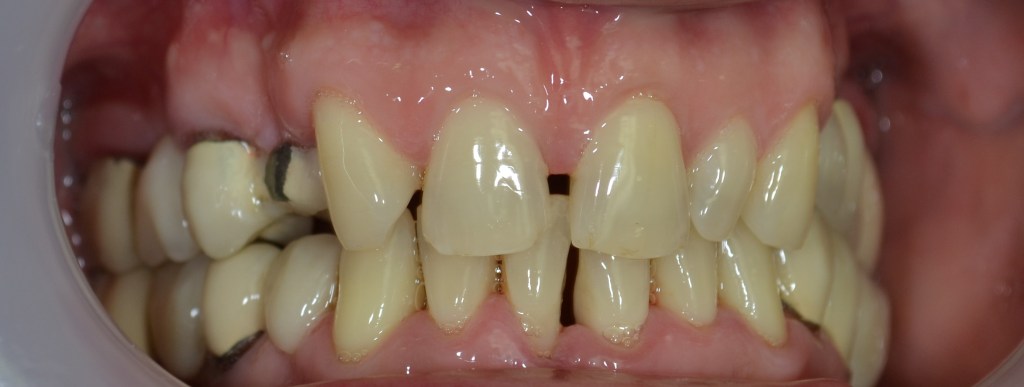

Kozmetikai kezelés: régi tömött, szuvasodott frontfogak szanálása, koronával történő leplezése, megsüllyedt harapás korrekciója.

A választott korona típusa: E-max préskerámia (fémmentes) és cirkon szóló koronák kombinációja.

A választott fogszín A1 .

A protetikai munka elkészülésének ideje: 5 munkanap.